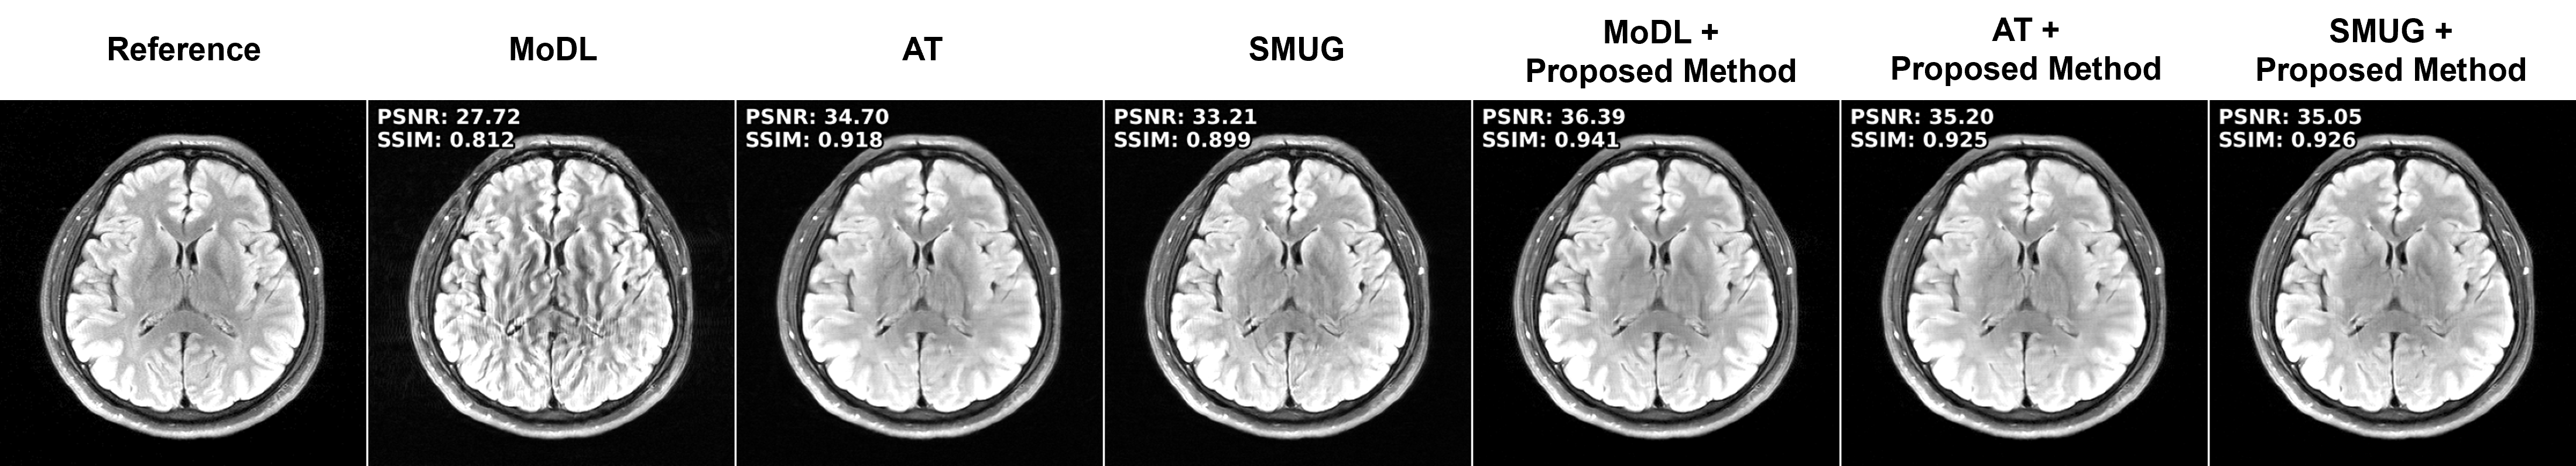

Figure 2: Representative reconstruction results for Cor-PD knee, and Ax-FLAIR brain MRI Datasets at R=4R=4. The attack inputs lead to severe disruption in the baseline MoDL reconstruction. Adversarial training improves these, albeit suffering from blurriness. SMUG fails to eliminate the attack. The proposed strategy reduces the artifacts and maintains sharpness. Furthermore it can be combined with the other strategies for further gains (last two columns).

4.2 Attack Mitigation Results

Performance Across Datasets. We first study our approach and the comparison methods on knee and brain MRI datasets at RR = 4. Fig. 2 shows that baseline PD-DL (MoDL) has substantial artifacts under attack. SMUG improves these but still suffers from noticeable artifacts. AT resolves the artifacts, albeit with blurring. Our proposed approach successfully mitigates the attacks

without any retraining, while maintaining sharpness. We note our method can also be combined with SMUG and AT to further improve performance. Fig. 4 summarizes the quantitative metrics for all test slices, consistent with visual observations.

Performance Across Attack Strengths and Blind Mitigation. We next test the methods across different attack strengths, ϵ\epsilon\in{0.01,0.02}\{0.01,0.02\}. Fig. 3 shows the results for both attack strengths using the robust training methods trained with ϵ\epsilon = 0.01 and proposed mitigation. As in Fig. 2, SMUG has artifacts at ϵ\epsilon = 0.01, which gets worse at ϵ\epsilon = 0.02. Similarly, AT struggles at ϵ\epsilon = 0.02, since it was trained at ϵ\epsilon = 0.01, leading to visible artifacts (arrows). On the other hand, our training-free mitigation is successful at both ϵ\epsilon.